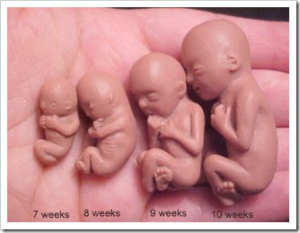

7 semanas de gravidez

8 semanas de gravidez

9 semanas de gravidez

10 semanas de gravidez

- Com 10 semanas de gestação o bebê já está a mil dentro do útero, porém as mamães ainda não conseguem sentir os movimentos devido ao seu tamanho, que chega em média a 3,1 cm!

Com 10 semanas de gestação o bebê já está a mil dentro do útero, porém as mamães ainda não conseguem sentir os movimentos devido ao seu tamanho, que chega a 3,1 cm! É ainda muito pequeno, mas não é mais considerado um embrião e a parte mais perigosa da formação e da gravidez também já está no final. Agora a sua cabeça começa a ficar proporcional ao corpo, diferente da semana anterior1.

Com 10 semanas de gestação, ele cresce a olhos vivos e para orgulho da mamãe dedica a maior parte do seu tempo a peraltices como esticar mãos e pernas e engolir líquido amniótico. A sua coluna já está desenhada e no ultrassom dá para ver os contornos, assim como da medula espinhal, que está em formação. Seus rins já funcionam a pleno vapor e todo líquido amniótico que o bebê engole é filtrado por eles, em uma espécie de treinamento para quando vier ao mundo2.

Nesta etapa de desenvolvimento das 10 semanas, os principais órgãos já estão formados e é também quando as unhas e os minúsculos fios de cabelo começam a surgir. Sua genitália está em processo de finalização e será possível em breve distinguir através do exame de ultrassonografia. Nesta semana, seu futuro bebezinho tem o tamanho de uma pequena azeitona.